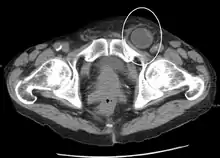

An incarcerated inguinal hernia as seen on cross sectional CT scan

An inguinal hernia which contains part of the bladder. Bladder cancer also present.

When assessed by ultrasound or cross sectional imaging with CT or MRI, the major differential in diagnosing indirect inguinal hernias is differentiation from spermatic cord lipomas, as both can contain only fat and extend along the inguinal canal into the scrotum.[22]

On axial CT, lipomas originate inferior or lateral to the cord, and are located inside the cremaster muscle, while inguinal hernias lie anteromedial to the cord and are not intramuscular. Large lipomas may appear nearly indistinguishable as the fat engulfs anatomic boundaries, but they do not change position with coughing or straining.[22]